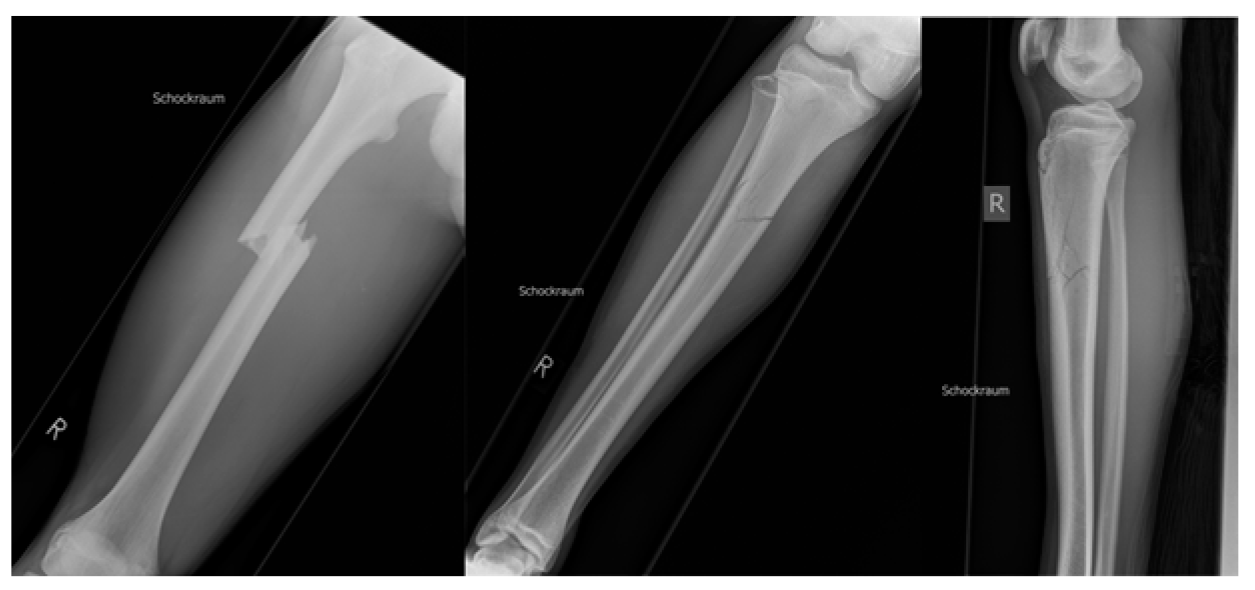

2. Case Description